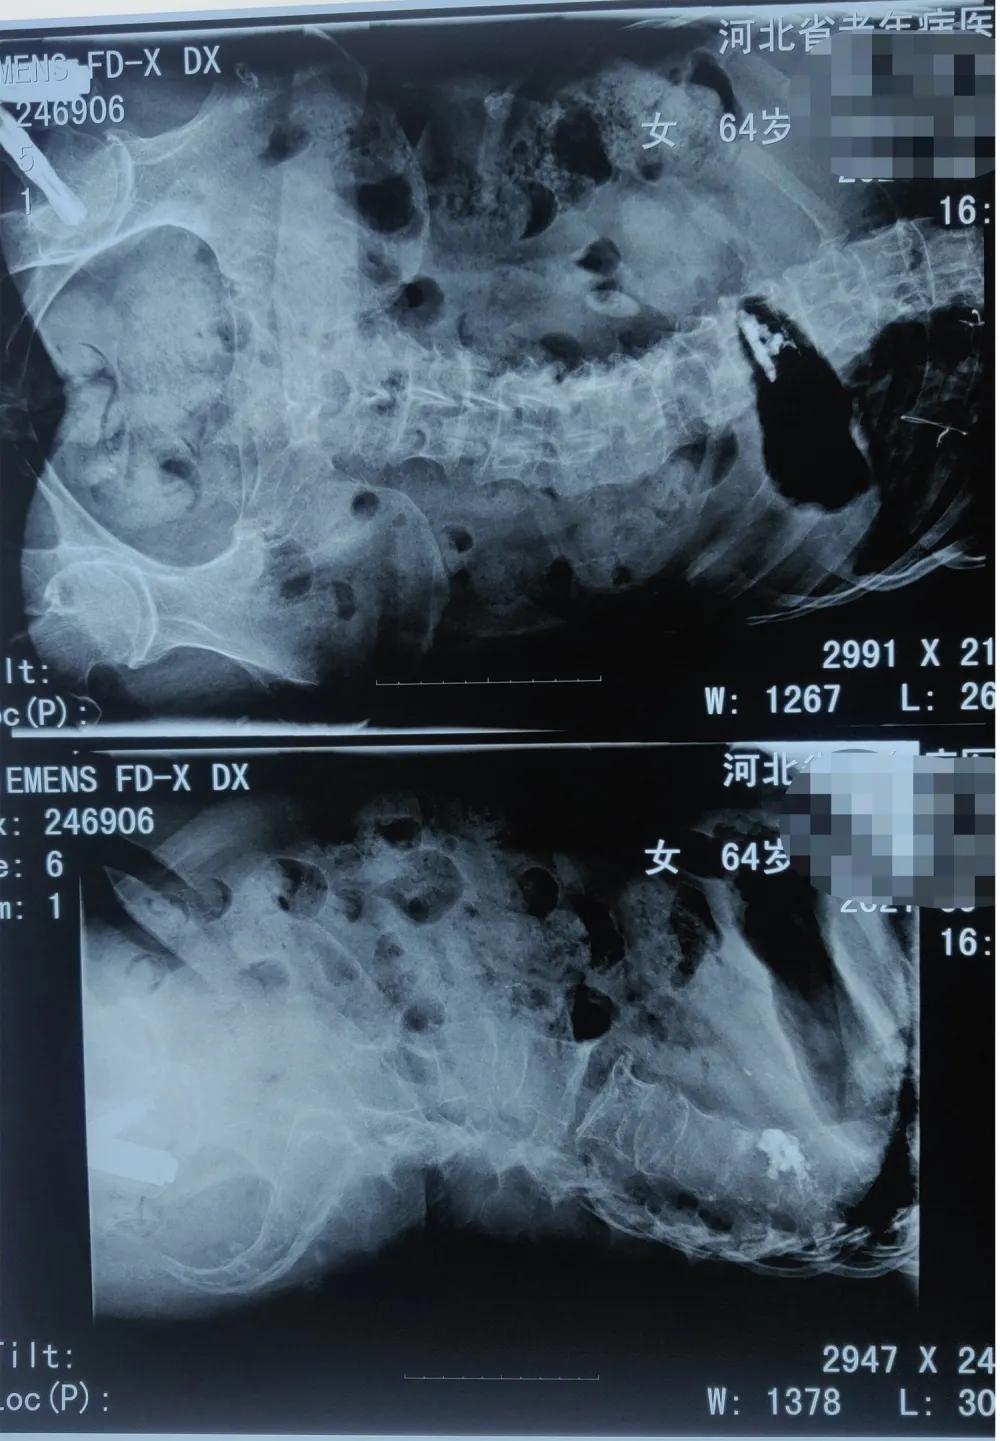

为缓解患者腰部疼痛症状,骨一科医师团队为患者进行了经皮穿刺椎体成形术。术后第二天,患者开心地说:“不疼了,不疼了,起床翻身感觉不到疼痛了!”

手术前

手术后

目前,针对骨质疏松性椎体压缩性骨折的治疗主要是采用经皮椎体成形术,就是将骨水泥注入骨折椎体内,从力学上增强其结构强度。相对于传统的保守治疗,该手术具有伤口小、愈合瘢痕小、出血少、术后疼痛轻、恢复快等特点,是老年椎体骨折患者的首选治疗方案。患者术后可立即下地,避免了长期卧床带来的诸如肺炎、压疮、尿路感染等并发症和护理不便。术后患者早期即可恢复自理能力,减轻家人的陪护负担和经济压力。